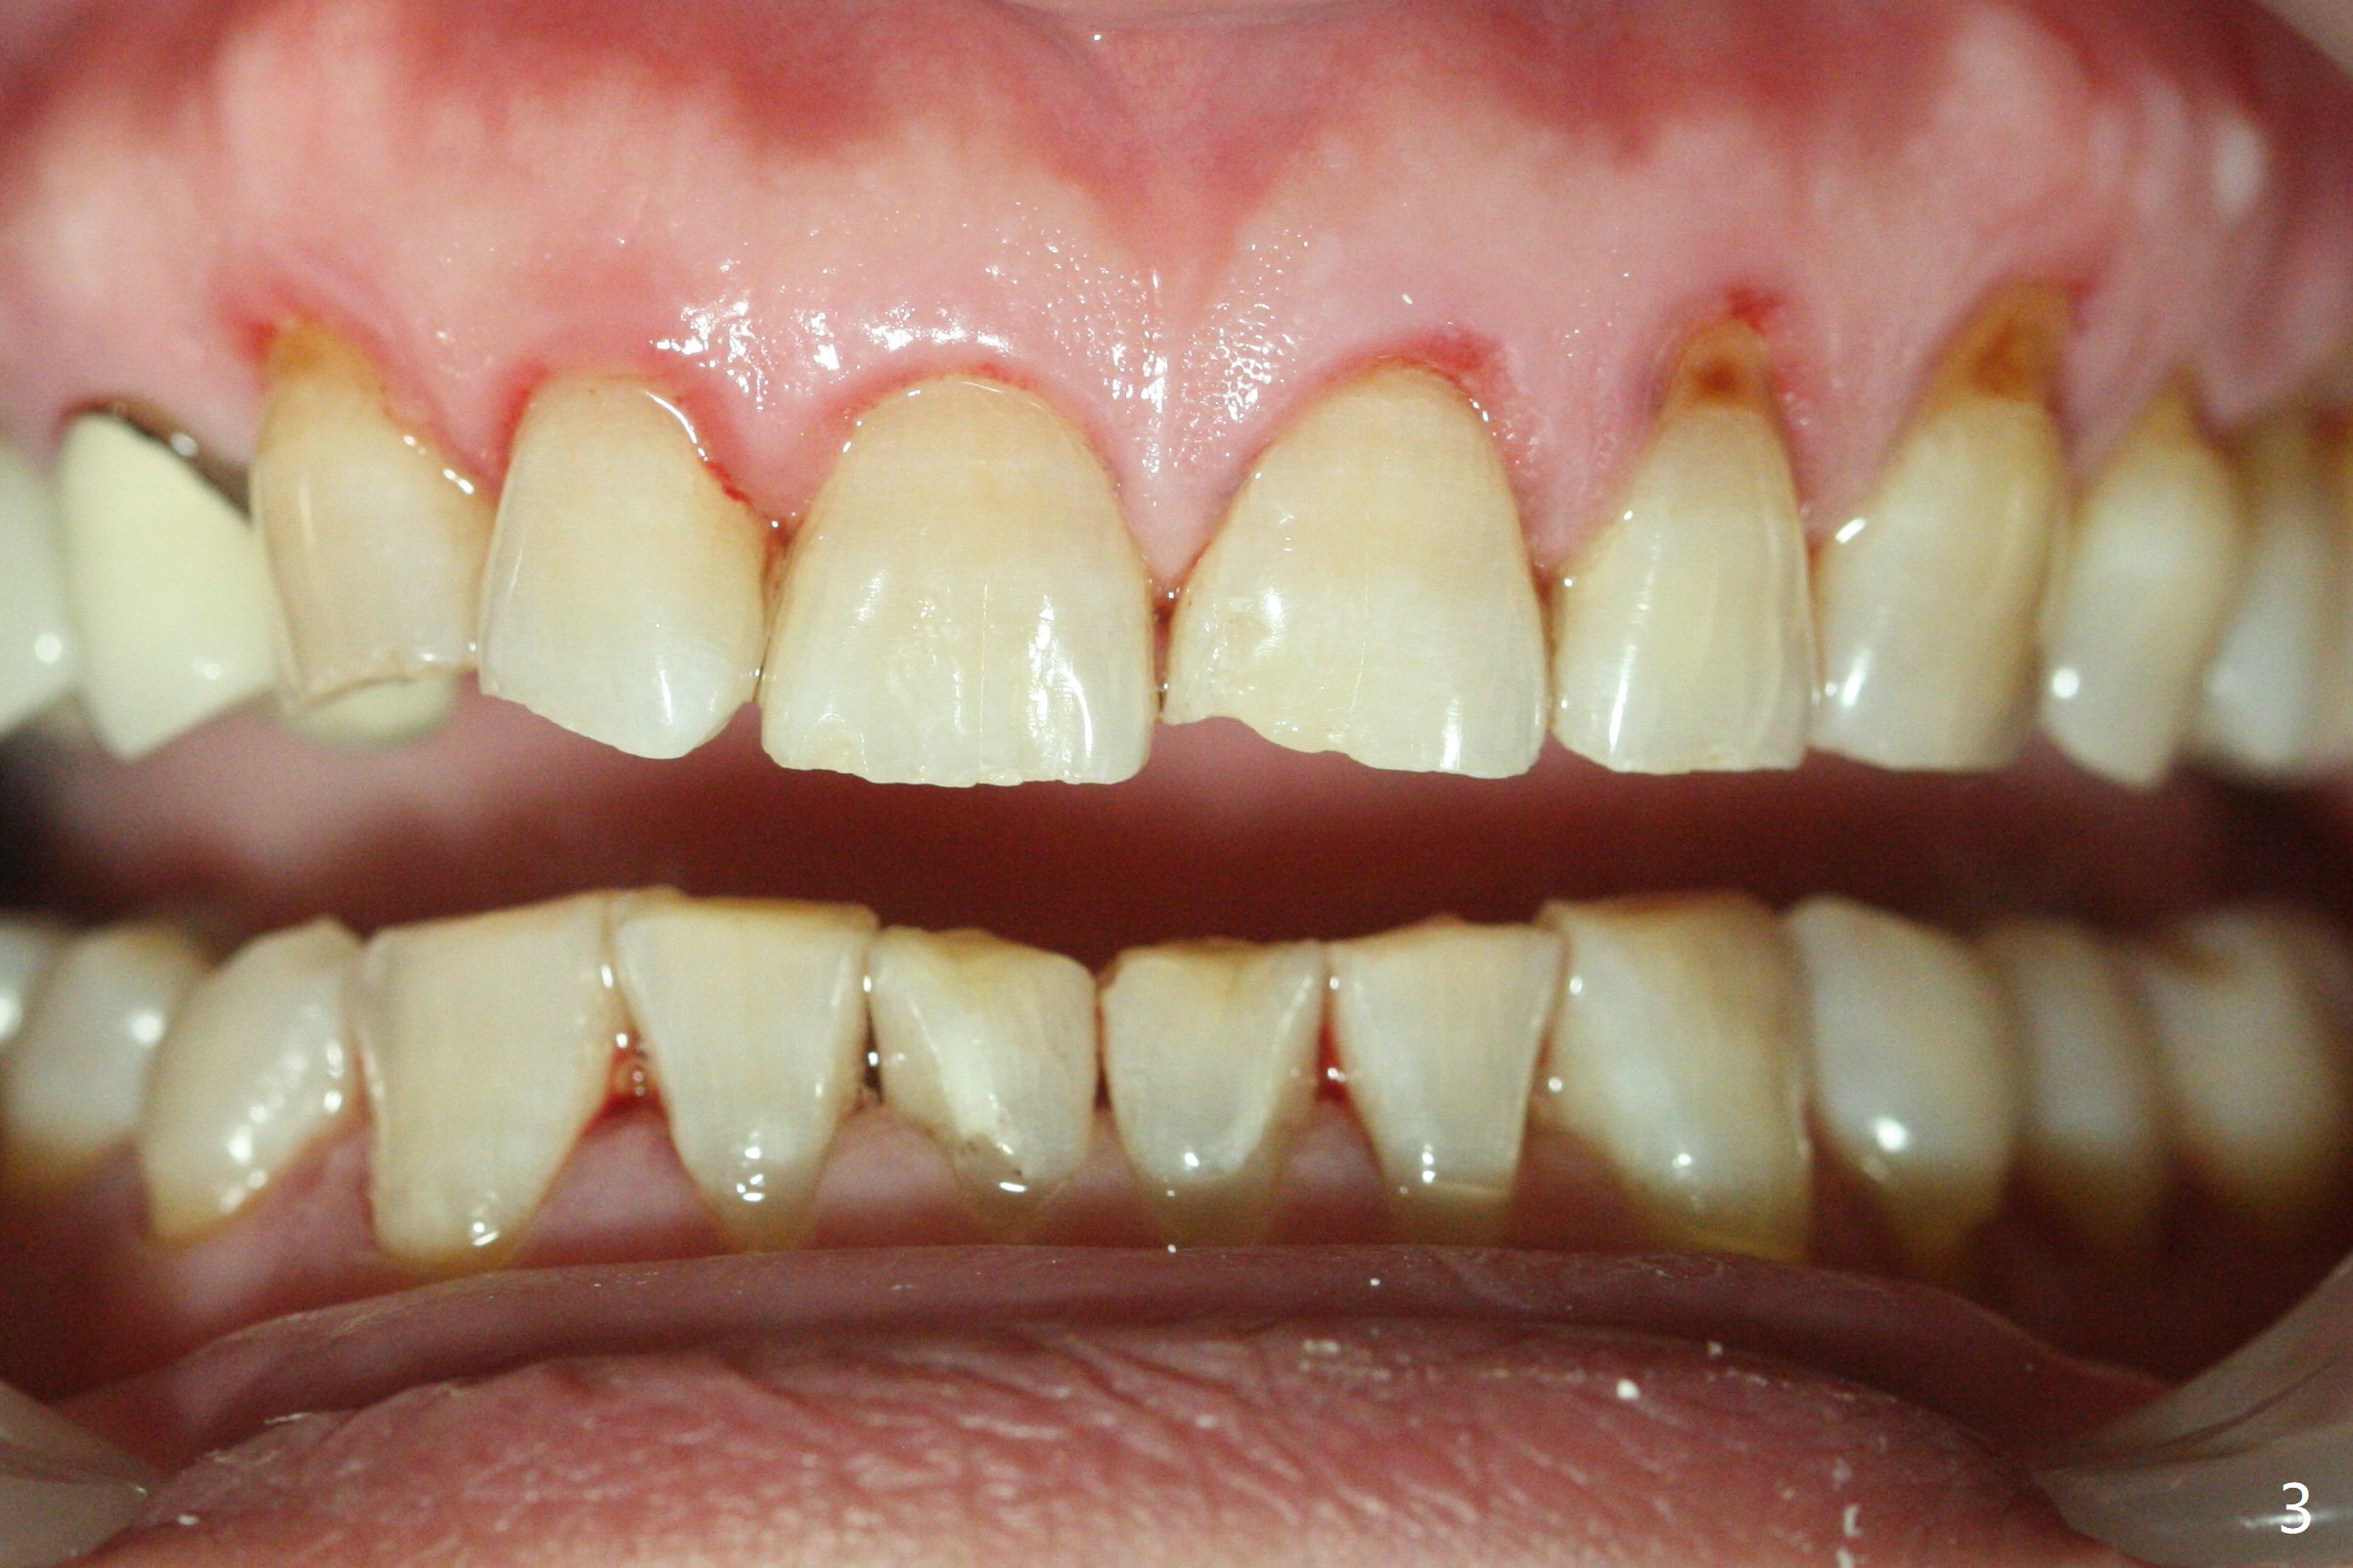

A 54-year-old man returns to office for UL7 upright 6 months post UR5 implant crown cementation (Fig.5,6). The ultimate purpose is to place implants at UL6 and LL 7. The latter will reduce severe occlusal wear especially in the lower anterior teeth (Fig.3,4). To solve the diastema between UR3 and 4 (Fig.1), the bracket at UR3 is placed in the height of contour (Fig.1 insert, Fig.4). Arch wire sequence may automatically close the diastema (Fig.1 insert arrows). In addition to tilting of UL7 (Fig.7), there are diastemata between U1s and UL3 and 4 (Fig.8,9 arrowheads). The patient is not tolerating orthodontic treatment well and requesting finishing the treatment early. We are considering mesializing UL7 instead of upright by placing a mini-implant between UL4 and 5 (Fig.10). There will be less interference of the roots of UL7 with the crown of the impacted UL8. There appears more space for a 1.6x8 mm mini-implant between UL4 and 5 (Fig.11) and UL 3 and 4 (Fig.12). Finally a mini implant is placed distal to UL7.